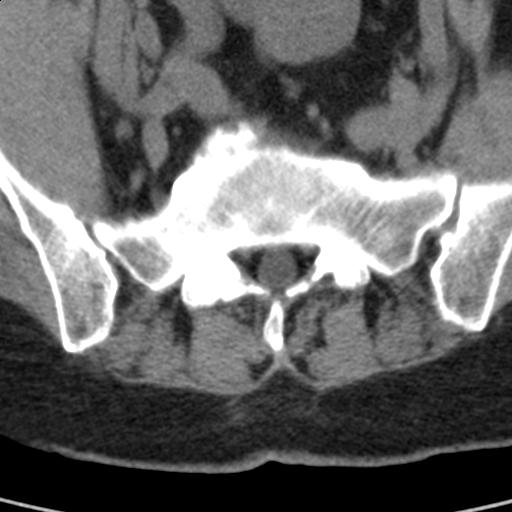

患者;女性;左下肢疼痛。

l5s1显示椎间盘突出,椎体边缘骨质增生,双侧黄韧带钙化。(请上传骨窗)

l5s1显示椎间盘突出,椎体边缘骨质增生,双侧黄韧带钙化 ,两侧椎小关节肥大,关节面硬化,关节间隙变窄,提示:椎小关节综合症

双侧的侧隐窝有狭窄。

我认为应该考虑为:l5s1椎间盘膨出,余(椎小关节退变、黄韧带钙化、椎间孔狭窄)与各位同行无异议。

l5s1显示椎间盘膨出,突出,椎体边缘骨质增生向后压迫硬膜囊,双侧黄韧带钙化,小关节面综合征

l5s1椎间盘向后脱出使脊膜囊受压,椎体边缘骨质增生,双侧黄韧带钙化。l45椎间盘估计亦突出,为何未扫。